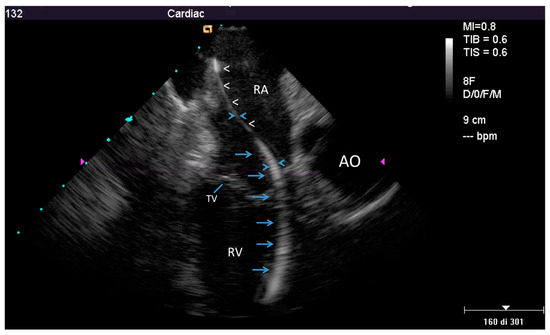

2.2.2. After the Extraction

3.2. Post-extraction ICE